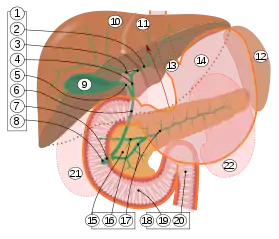

1. Voies biliaires : 2. Voies biliaires intrahépatiques, 3. Voies hépatiques gauche et droite, 4. Voie hépatique commune, 5. Conduit cystique, 6. Conduit cholédoque, 7. Ampoule de Vater, 8. Papille duodénale majeure

9. Vésicule biliaire, 10–11. Lobes droit et gauche du foie. 12. Rate.

13. Œsophage. 14. Estomac. 15. Pancréas : 16. Canal pancréatique accessoire, 17. Canal pancréatique.

18. Intestin grêle : 19. Duodénum, 20. Jéjunum

21-22. Reins droit et gauche.

La bordure avant du foie a été soulevée (flèche brune)[1].